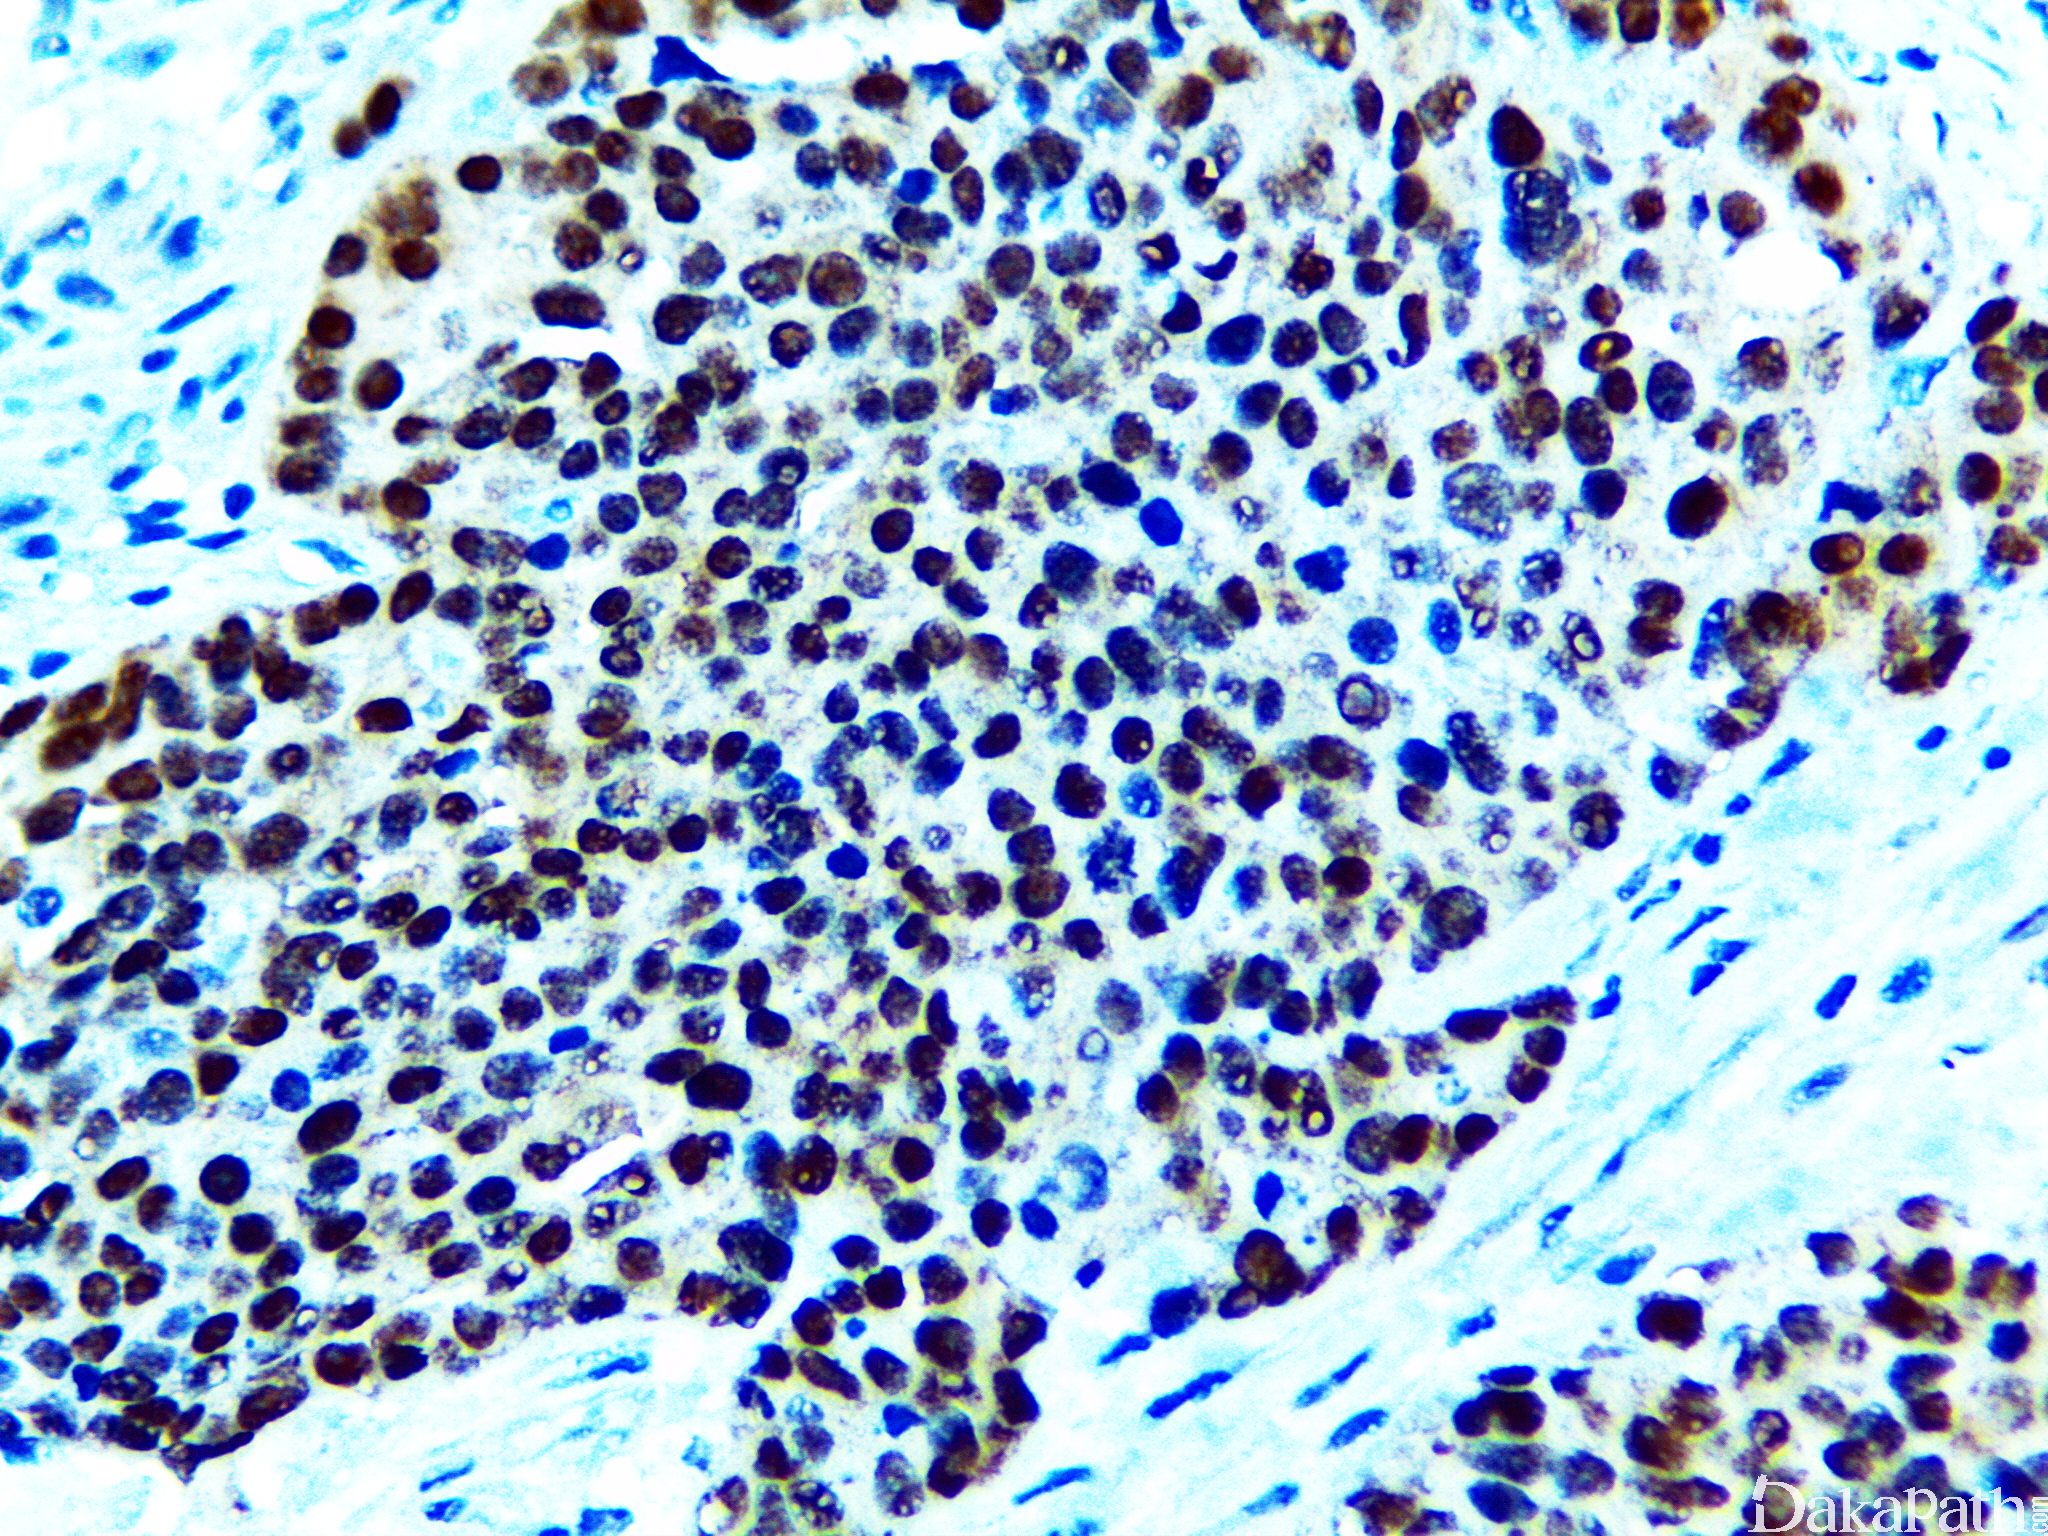

PAX8

核转绿因子,PAX(pair box gene)家族成员之一。表达于甲状腺、肾导管组织、副中肾管组织及相关肿瘤中,对于转移性肾细胞癌,PAX-8 的敏感性优于 CD10 和 RCC。

阳性表达主要见于肾肿瘤(肾细胞癌及肾集合管癌)、苗勒管肿瘤(80-85%)、甲状腺肿瘤;其它阳性表达肿瘤包括胸腺瘤/癌和胰腺神经内分泌肿瘤。

信号定位: 典型的为胞核阳性,胞质或包膜着色为非特异性着色。

几乎全部阳性(≥95%的病例阳性): 宫颈高级别鳞状上皮内病变、胸腺瘤,A 型、透明细胞乳头状肾细胞癌、乳头状肾细胞癌、肾混合性上皮和间质肿瘤,间质成分、肾细胞癌、透明细胞肾细胞癌、管囊性肾细胞癌、肾混合性上皮和间质肿瘤,上皮、甲状腺滤泡性腺瘤、子宫内膜腺癌,NOS、甲状腺滤泡性癌、甲状腺乳头状癌、良性胸腺瘤、甲状腺癌显示胸腺样分化、卵巢低级别浆液性癌、肾母细胞瘤、子宫内膜黏液腺癌、卵巢高级别浆液性癌、淋巴瘤、膀胱透明细胞癌、宫颈透明细胞癌、卵巢恶性 brenner 瘤、阴道透明细胞腺癌,DES 相关、肾横纹肌样肾细胞癌,横纹肌样成分、肾髓质癌、高分化乳头状间皮瘤、甲状旁腺腺瘤、卵巢透明细胞癌、甲状腺腺瘤、卵巢浆液性交界性肿瘤/非典型增生性浆液性肿瘤、肾混合性间质和上皮肿瘤、中肾腺瘤、囊性肾瘤、宫颈原位腺癌、卵巢浆液性癌、肾黏液管状和梭形细胞癌、肾源性腺瘤、卵巢表面上皮包涵腺体和囊肿